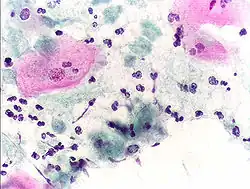

High-grade squamous intraepithelial lesion

In the United States, about 2–3 million abnormal Pap smear results are found each year.[31] Most abnormal results are mildly abnormal (ASC-US (typically 2–5% of Pap results) or low-grade squamous intraepithelial lesion (LSIL) (about 2% of results)), indicating HPV infection. Although most low-grade cervical dysplasias spontaneously regress without ever leading to cervical cancer, dysplasia can serve as an indication that increased vigilance is needed.

In a typical scenario, about 0.5% of Pap results are high-grade SIL (HSIL), and less than 0.5% of results indicate cancer; 0.2 to 0.8% of results indicate Atypical Glandular Cells of Undetermined Significance (AGC-NOS).

Abnormal results are reported according to the Bethesda system.[33] They include:[31]

• Atypical squamous cells (ASC)

• Atypical squamous cells of undetermined significance (ASC-US)

• Atypical squamous cells – cannot exclude HSIL (ASC-H)

• Squamous intraepithelial lesion (SIL)

• Low-grade squamous intraepithelial lesion (LGSIL or LSIL)

• High-grade squamous intraepithelial lesion (HGSIL or HSIL)

• Squamous cell carcinoma

• Glandular epithelial cell abnormalities

• Atypical glandular cells not otherwise specified (AGC or AGC-NOS)

Endocervical and endometrial abnormalities can also be detected, as can a number of infectious processes, including yeast, herpes simplex virus and trichomoniasis. However it is not very sensitive at detecting these infections, so absence of detection on a Pap does not mean absence of the infection.[34]